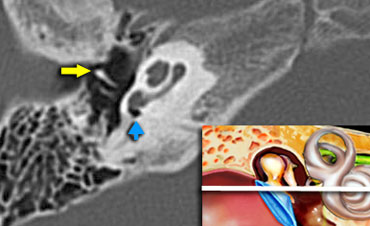

Tympanic membrane

The manubrium of the malleus (yellow arrow) is connected to the tympanic membrane.

At this level we can see the manubrium of the malleus (yellow arow) anterior to the long process of the incus.

The round window is indicated by the blue arrow.

The round window dissipates the pressure generated by the fluid vibrations within the cochlea and thus serves as a release valve.